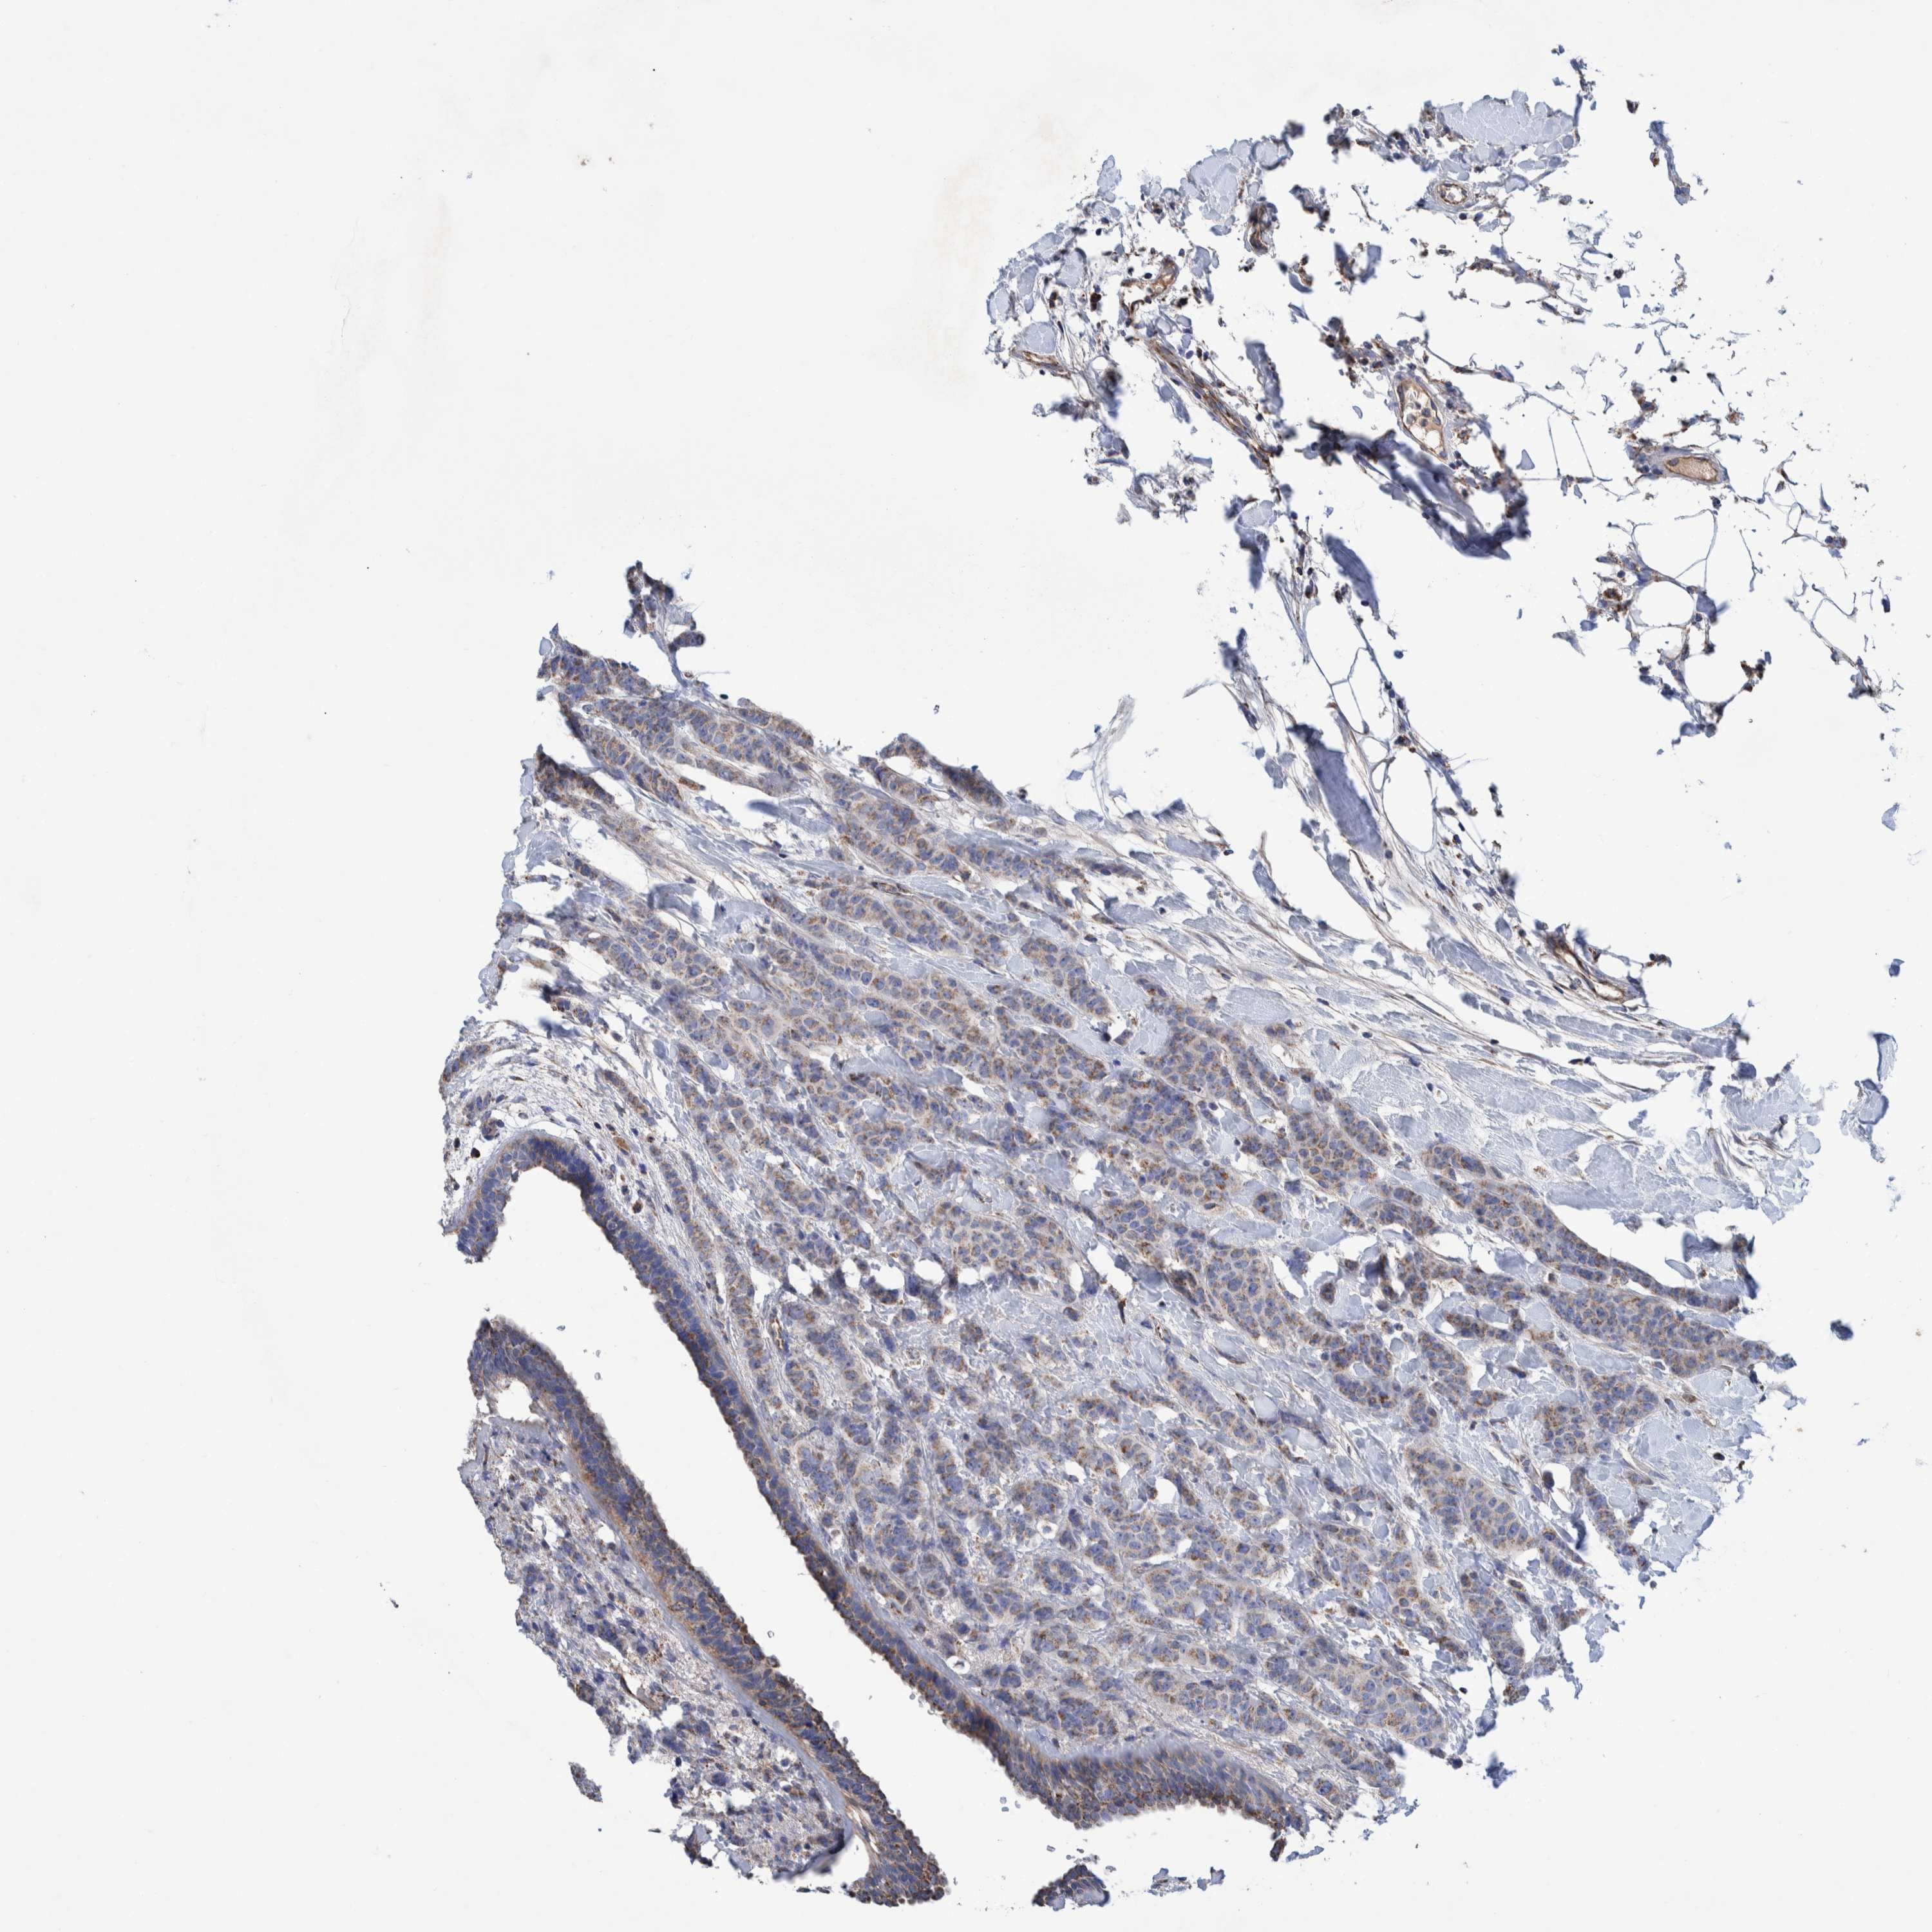

CANCER BREAST CANCER Show tissue menu

Breast cancer

Human cancer